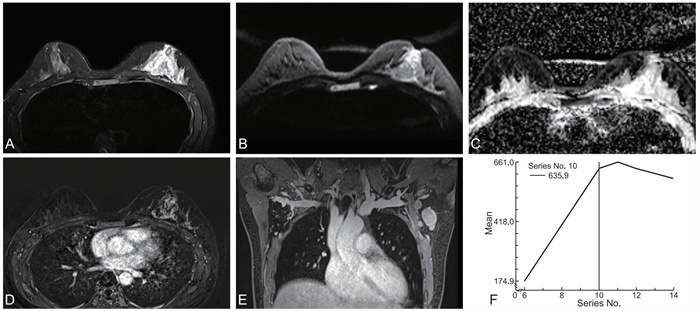

基于临床及CT征象的列线图术前预测肺腺癌组织学分级的价值

叶媛鑫, 刘璐璐, 潘婷, 江海涛

2025, 23(10): 1743-1747. doi: 10.16766/j.cnki.issn.1674-4152.004219

2 0

摘要:

目的  探索CT影像学特征和临床信息与肺浸润性非黏液腺癌病理组织学分级之间的关系,构建预测组织学分级的模型,并进行模型可视化。  方法  收集2021年7—12月浙江省肿瘤医院收治的肺浸润性非黏液腺癌患者313例,按照组织学分级分为中低级别组和高级别组。收集患者临床资料及CT影像学资料,进行统计学分析,分别建立影像学模型和联合模型,绘制列线图和ROC曲线计算AUC,并使用DeLong检验进行比较。  结果  多因素分析显示,CT影像学的长径、实性成分长径、实性比例、空气支气管征均为组织学分级的影响因素(P<0.05),建立影像学模型,AUC为0.879;纳入临床资料及CT影像学征象进行多因素分析,结果显示,吸烟、神经元特异性烯醇化酶(NSE)、长径、实性成分长径、实性比例、空气支气管征均为组织学分级的影响因素(P<0.05),建立联合模型,AUC为0.899。DeLong检验显示影像模型和联合模型AUC差异无统计学意义(P=0.070)。  结论  CT及血清肿瘤学指标对鉴别肺浸润性非黏液腺癌的中低级别和高级别具有一定的预测价值,有望在术前预测浸润性腺癌的组织学分级。